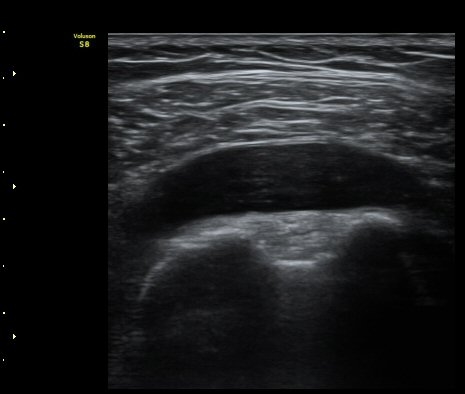

¾î±ú À̵ιڱ٠Ⱦ´Ü¸é°Ë»ç¿¡¼­ ½ÉÇÑ Á¡¾×³¶³» ¼ö¾×Àú·ù°¡ °üÂûµÇÁö¸¸ ÆÄ¿öµµÇ÷¯

°Ë»ç¿¡¼­ Ç÷·ùÁõ°¡´Â °üÂûµÇÁö ¾Ê´Â´Ù(±×¸² 1, 2).   À̵ιڱ٠¾Æ·¡ Ⱦ´Ü¸é°Ë»ç¿¡¼­